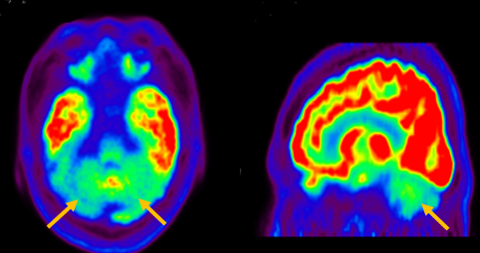

다계통 위축이란 뇌의 다양한 계통에서 위축이 발생하는 것을 의미합니다. 파킨슨 증상이 있으면서 질병 초기에 소변 장애나 기립성 저혈압으로 인한 어지러움이 두드러지게 나타나는 경우, 보행 시 비틀거림이나 구음 장애와 같은 소뇌 위축에 따른 운동 실조 증상이 나타나는 경우, 꿈에서 하는 행동을 수면 중에 보이는 렘수면 행동 장애가 동반되는 경우 다계통 위축을 의심합니다. 다계통 위축은 파킨슨병과 달리 안정 시 떨림이 잘 보이지 않고, 증상이 대칭적인 경우가 많으며, 진행이 빠르며, 레보도파와 같은 항파킨슨 약제에 잘 반응하지 않습니다. 다계통 위축은 뇌 자기공명영상(MRI)에서 교뇌에 십자 모양의 고음영이 나타날 수 있는데, 이를 십자무늬 빵(hot cross bun) 징후라고 합니다. 또한 초기에서는 뇌 자기공명영상(MRI)이 정상으로 보이더라도 뇌포도당 양전자 단층촬영(PET)에서는 소뇌 또는 기저핵의 대사 기능이 저하된 상태가 관찰될 수 있습니다. 이러한 영상 소견은 특징적인 임상 증상과 함께 진단에 참고할 수 있습니다.

[다계통위축 환자의 뇌자기공명영상에서 확인되는 십자무늬빵 징후]

[다계통위축 환자의 뇌포도당 양전자 단층 촬영에서 확인되는 소뇌의 대사 기능 저하]3. 피질 기저핵 변성(Corticobasal degeneration)